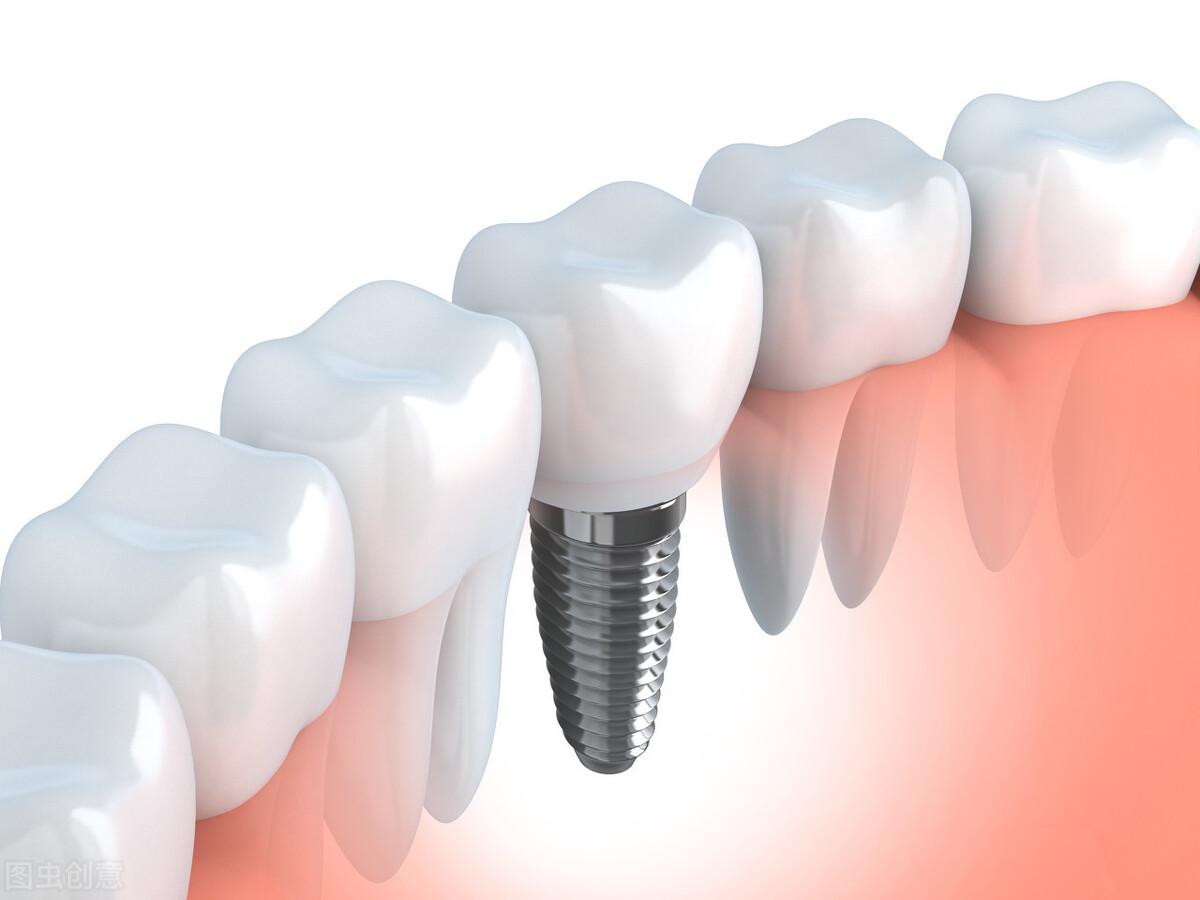

種植牙,全稱為人工種植牙,分成三個(gè)部分:種植體(人工牙根)、基臺(tái)(連接體)和牙冠(牙齒)。

種植體是一種高度精密的螺絲構(gòu)造,它外部的螺紋和微表面結(jié)構(gòu)與牙床骨接觸,引導(dǎo)牙床骨細(xì)胞生長(zhǎng)到種植體表面,以達(dá)到種植體與牙床骨充分結(jié)合,增強(qiáng)其咀嚼力量及穩(wěn)定性能的目的。